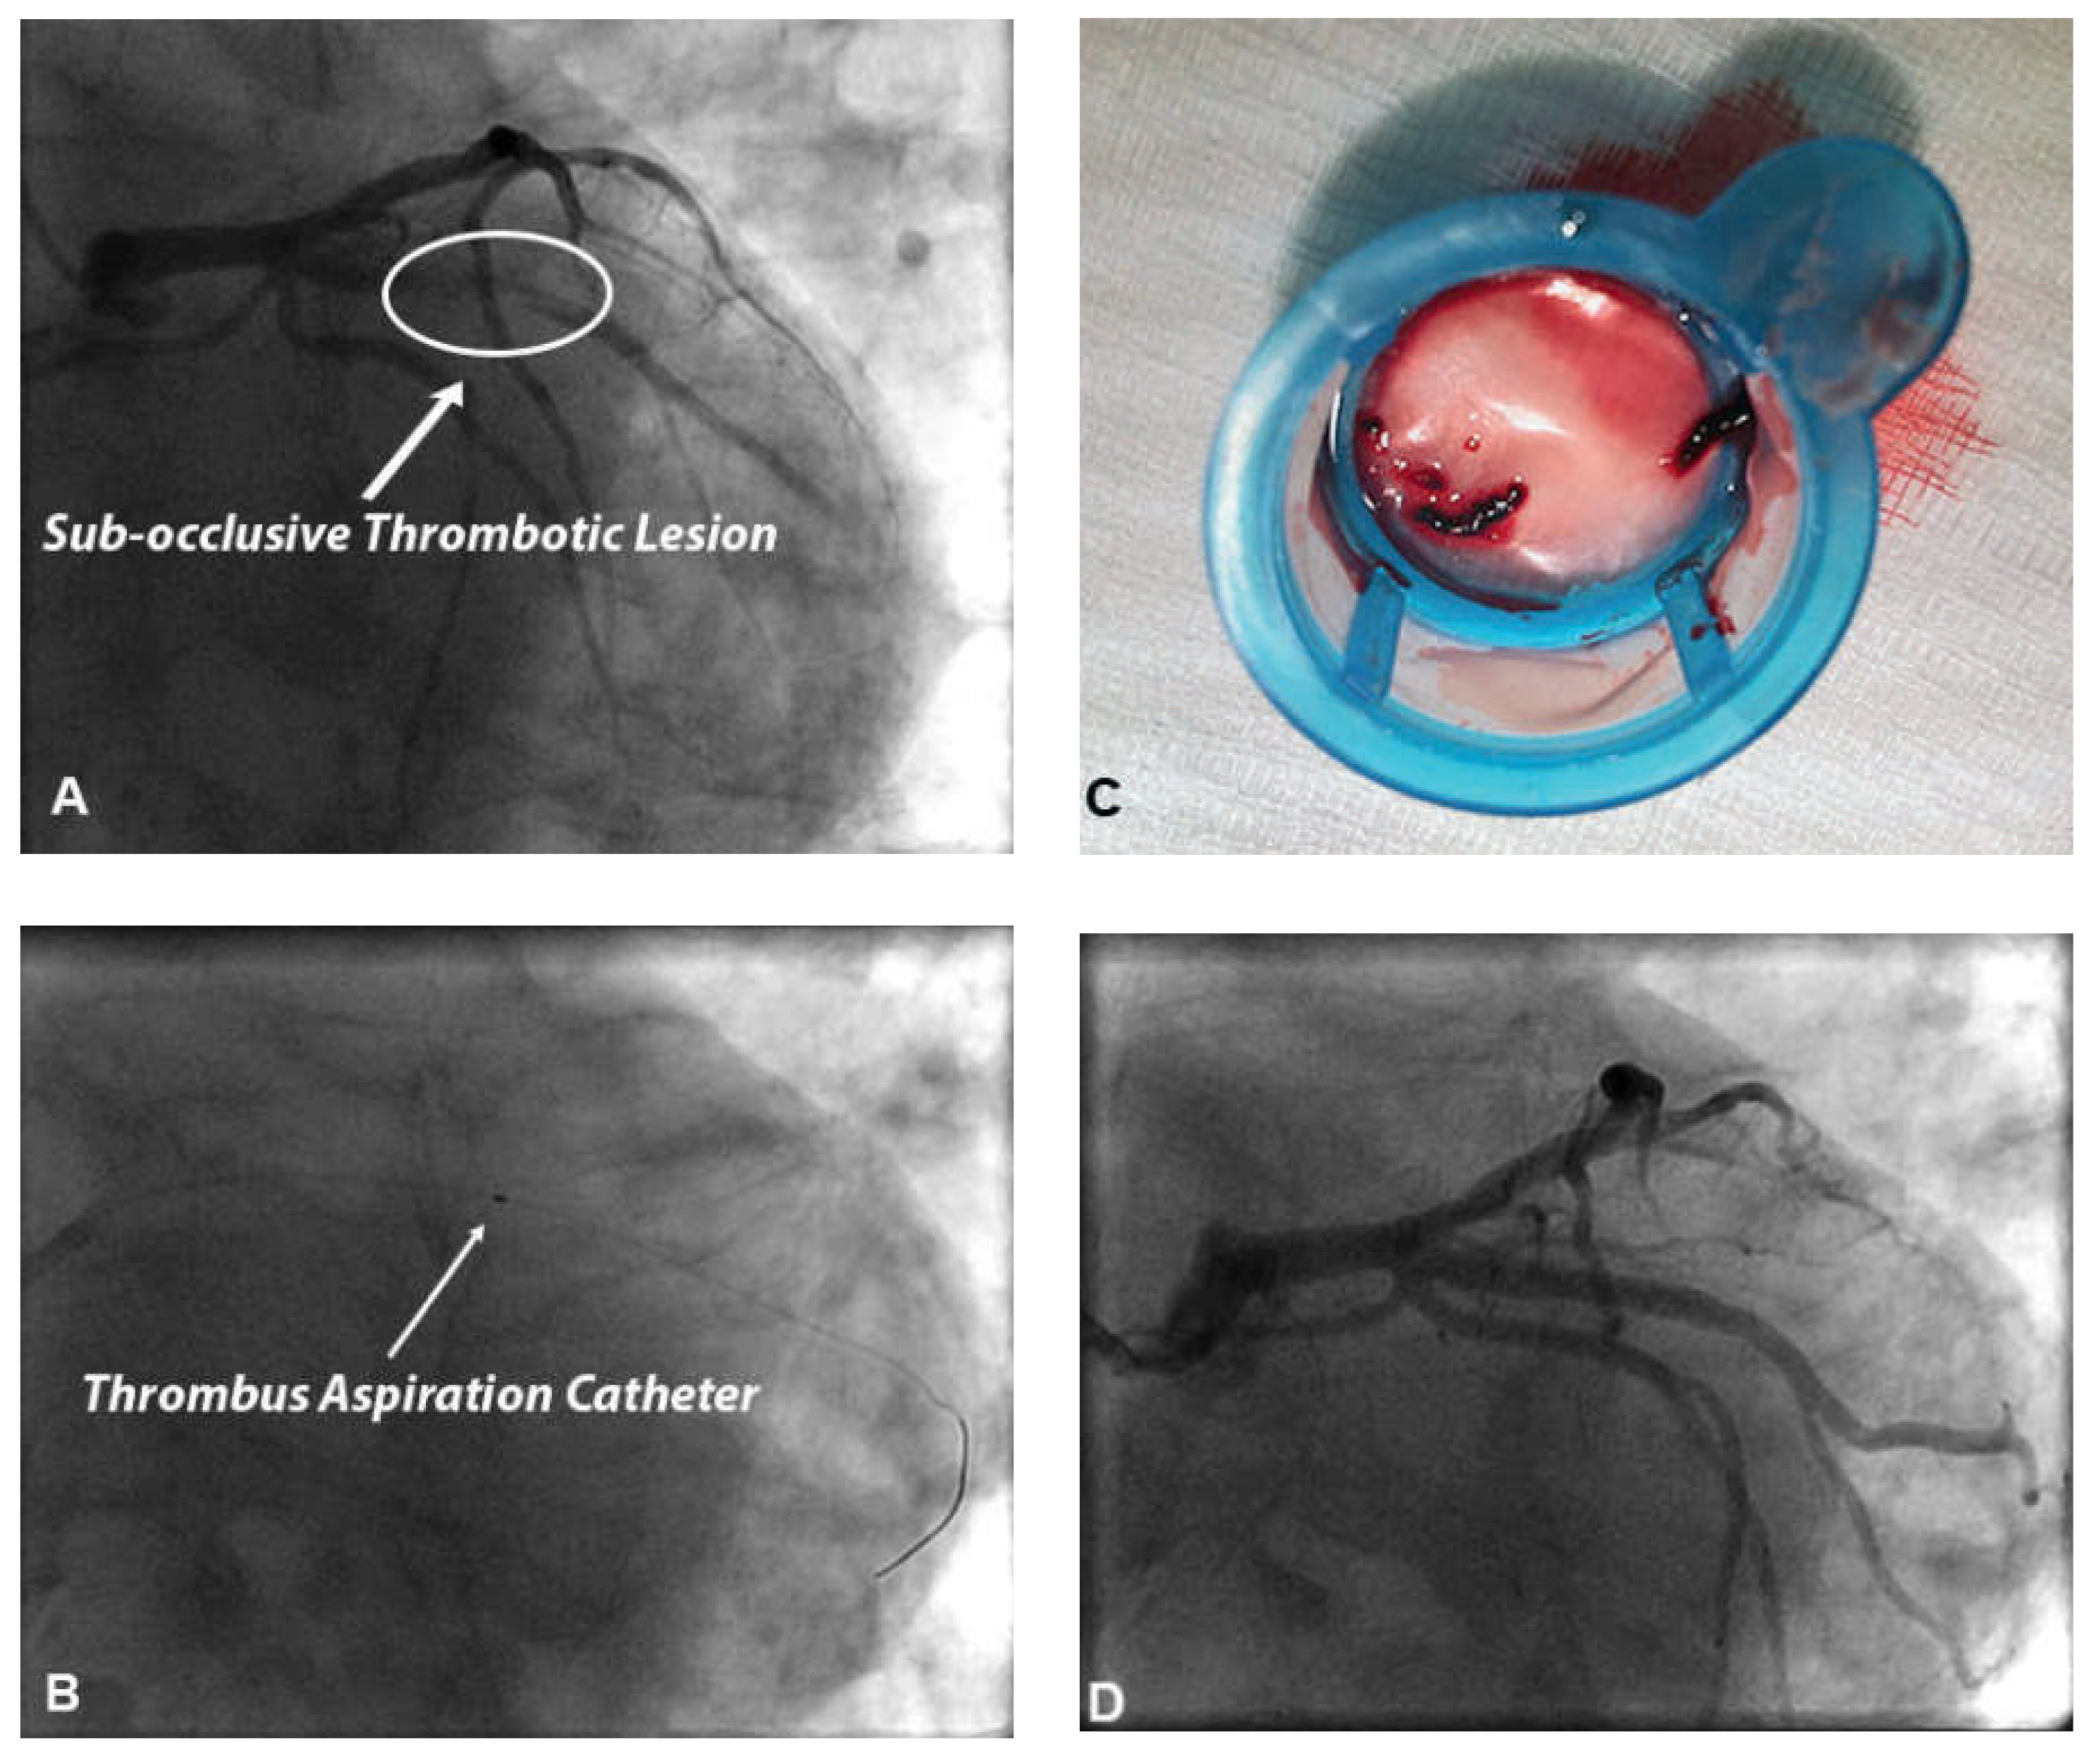

Figure 1. Panel A. Coronary angiography of an 82-year-old smoking, hypertensive and dyslipidaemic patient presenting to the emergency department for typical chest pain. Angiography shows a subocclusive thrombotic lesion of the proximal portion of first marginal artery. Panel B. After guidewire crossing of this thrombotic lesion, a thrombus aspiration catheter was advanced into the mid portion of first marginal artery beyond the thrombus. Panel C. Thrombotic material retrieved from culprit coronary plaque. Panel D. After thrombus aspiration a percutaneous coronary intervention (PCI) was performed. The patient underwent direct stenting with drug-eluting stent implantation. Good final angiographic result with a post-PCI TIMI flow 3.

The use of manual or mechanical thrombectomy devices to reduce the risk of distal embolisation during pPCI has been investigated in several clinical trials. Manual thrombectomy is usually performed using dedicated catheters compatible with a 6 or 7 French guiding catheter on 0.014’’ guide-wires and allows direct retrieval of intraluminal thrombus (Figure 1). Mechanical thrombectomy devices like Angiojet® use high-pressure backward saline jets to create a vacuum at the tip of the catheter to break up and remove thrombus.